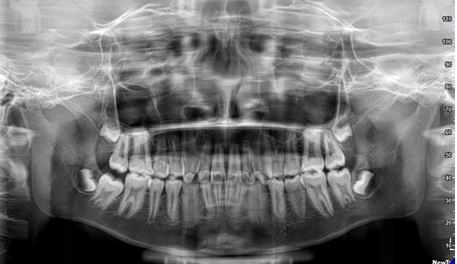

Pretreatment orthopantomogram revealed three roots in maxillary first premolar teeth bilaterally which was further confirmed by Intraoral periapical (IOPA) radiograph (Figure 4). The permanent first and second molars of all the four quadrants presented with enlarged pulp chambers with unusual cervical constriction and shortened roots indicating taurodontism. Taurodontism was evaluated using Shifman and Chanannel method.13 Taurodontism was diagnosed if calculated index was more than 20%. Taurodontism index for first and second molar teeth are tabulated in Table 1.

Figure 4 Orthopantomogram.